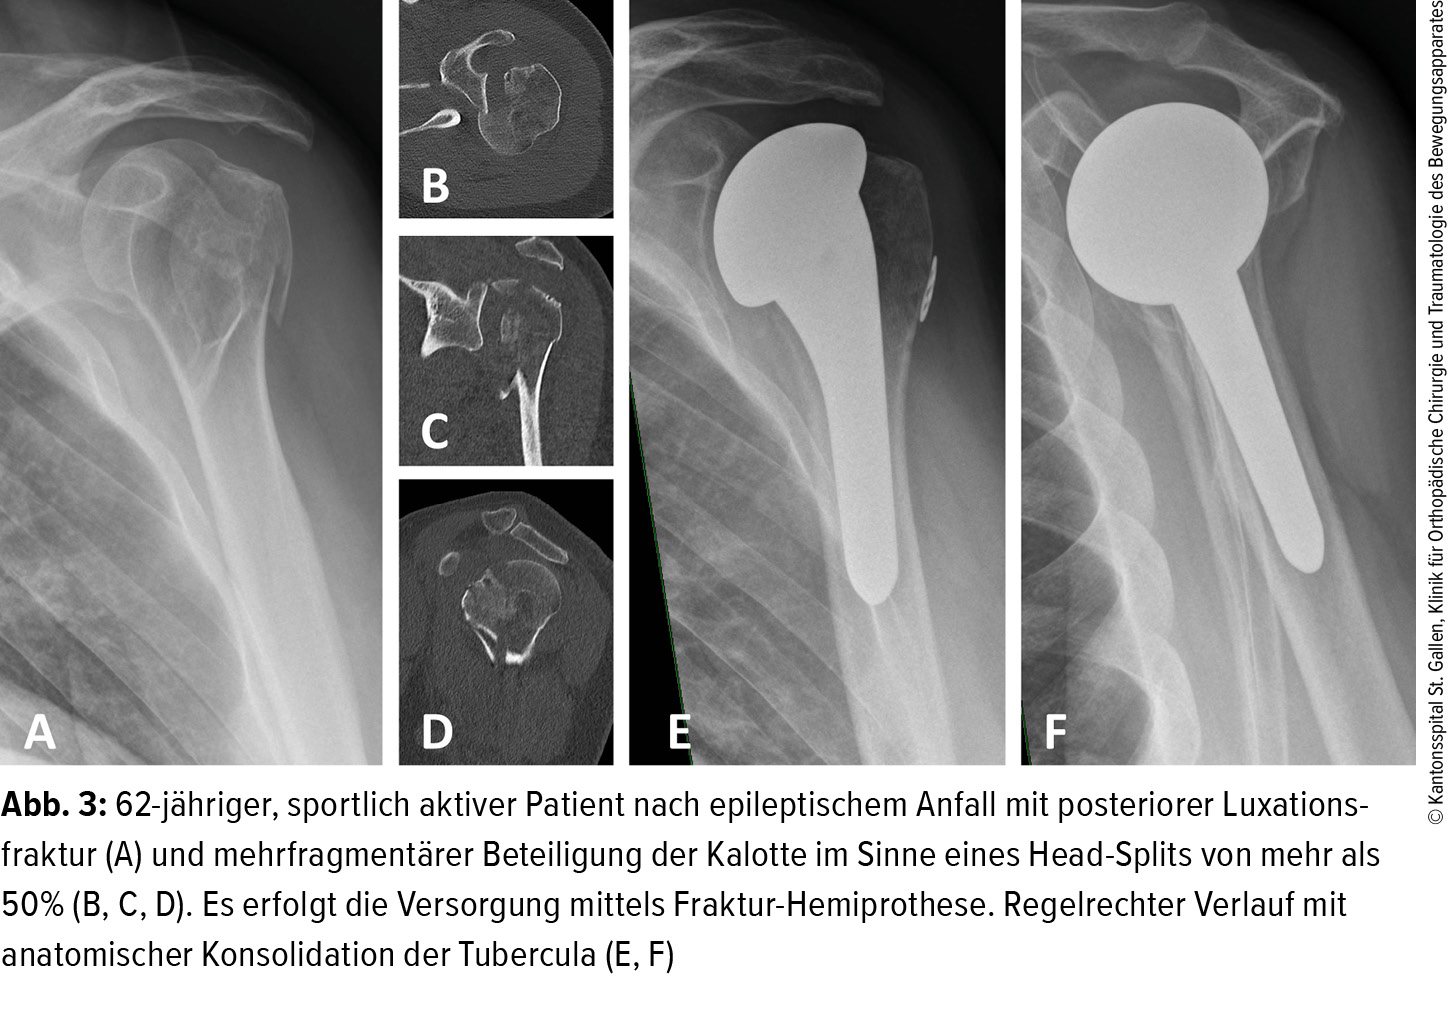

Frakturprothetik der Schulter - Orthopädie & Traumatologie - Universimed - Medizin im Fokus